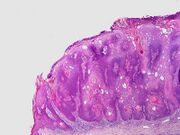

Micrograph of a seborrheic keratosis (H&E stain, scanning magnification)

Visual diagnosis is made by the "stuck on" appearance, horny pearls or cysts embedded in the structure. Darkly pigmented lesions can be challenging to distinguish from nodular melanomas.[10] Furthermore, thin seborrheic keratoses on facial skin can be very difficult to differentiate from lentigo maligna even with dermatoscopy. Clinically, epidermal nevi are similar to seborrheic keratoses in appearance. Epidermal nevi are usually present at or near birth. Condylomas and warts can clinically resemble seborrheic keratoses, and dermatoscopy can be helpful to differentiate them. On the penis and genital skin, condylomas and seborrheic keratoses can be difficult to differentiate, even on biopsy.[بحاجة لمصدر]

A study examining over 4,000 biopsied skin lesions identified clinically as seborrheic keratoses showed 3.1% were malignancies. Two-thirds of those were squamous cell carcinoma.[11] To date, the gold standard in the diagnosis of seborrheic keratosis is represented by the histolopathologic analysis of a skin biopsy.[12]